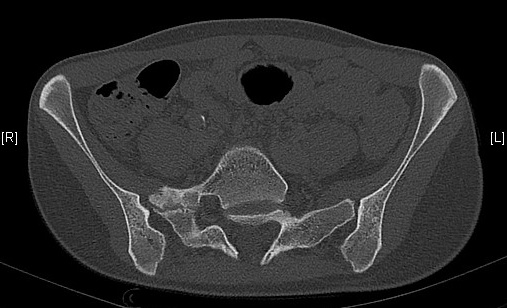

Néo-articulation transverso-sacrée droite